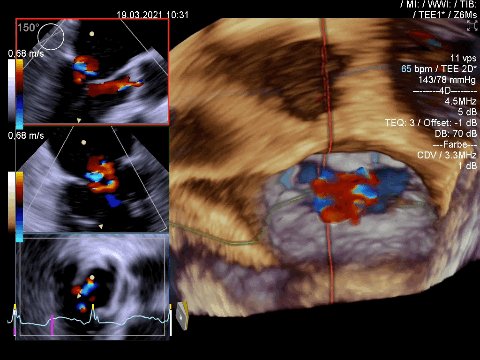

but once #echofirst made clear that there is significant pathology with consecutive enlargement of LV and LA we must hunt down the jet, here we see 2 jets. Now call for TEE or can we proceed with TTE?

#echofirst TEE goes 3D, important to start from good 2D, optimize resolution using 4D zoom preparation, take landmarks for orientation, better taking more 3D datasets (me taking always from all 3 apical views)

Most important #echofirst step b4 activating 4D is to optimize the 2 planes. Must capture whole zone of interest with orientation landmarks for MV aortic valve and LAA.

#echofirst shows with surgical orientation (AV at 12) the defects, bileaflet lesion. Post processing 🔑 to magic:

1/6 #echofirst meets 3D when looking at mitral valve & regurgitation. Blood pressure during exam around 140 mmHg

2/6 visualizing mitral valve (surgical perspective) with AV at 12 ⌚️ and LAA at 9 ⌚️

3/6 visualizing central color jet, dataset slightly tilted to appreciate better it´s relation to the commissure